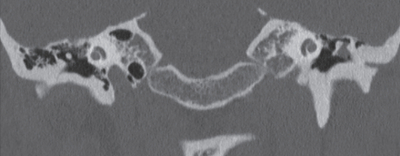

36 歳の女性。左耳の聞こえにくさを主訴に来院した。数年前から左耳漏を繰り返していた。最近、聴力が低下してきたため受診した。左鼓膜所見と側頭骨単純 CT の冠状断像を別に示す。

治療として適切なのはどれか。